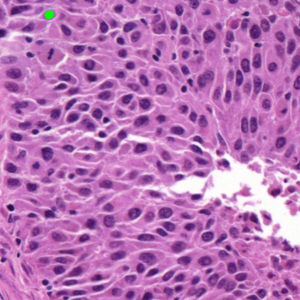

Dataset 3 consists of 50 annotated H&E-stained histological images from triple-negative breast cancer patients [74]. The images were acquired at 40× magnification using a Philips Ultra Fast Scanner (1.6RA) at the Curie Institute and contain a total of 4022 annotated cells.

Representative samples from the three datasets are shown in Fig. 1. In (a), the first frame of the synthetic video in Dataset 1 illustrates the strong illumination gradients produced by distance-dependent shading together with orientation-dependent interactions between vertex normals and the light direction. The H&E images in (b) and (c), also from Dataset 1, depict a mast cell infiltrate from a patient with non-alcoholic steatohepatitis and cirrhosis and, respectively, a sample from a patient with sclerosing polycystic adenosis of the parotid gland; the former consists primarily of purple nuclei, white cytoplasm, and pink extracellular tissue. Subfigures (d) and (e) show two examples from Dataset 2 accompanied by their ground-truth nuclei annotations, while (f) and (g) present a representative image from Dataset 3 together with its corresponding cell mask.

Figure 1: Samples from Datasets 1–3. (a) First frame of the 74-frame video in Dataset 1 (1770 × 880) with a superimposed red mesh. (b,c) H&E-stained tissue images from Dataset 1 (1000 × 750; 950 × 730). (d,e) Cell images from Dataset 2 (600 × 600) with nuclei annotations. (f,g) Image from Dataset 3 (512 × 512) with annotation.

Figure 5 shows an image from Dataset 3 with two different sets of markers. In the first case, Fig. 5(a,b), we manually placed five foreground seeds and one background seed; in the second case, Fig. 5(c,d), we slightly perturb the position of makers to test the stability of different models. Foreground and background seeds are labeled with the prefixes ‘f’ and ‘b,’ respectively, with the following number indicating their order (e.g., f2 denotes the second foreground seed). Note that there is only one background seed b1 in both cases. We then provided these to AR, SAM, and SP as markers.

Our model SP follows the selective variant from Section 5.3, with the target region number set equal to the number of markers. For SAM, we used the selective segmentation module in MATLAB 2024b. The AR model, while not requiring explicit background seeds, still needed background information; this was provided by assuming the domain outside the specified foreground was background. Since AR expects polygonal regions rather than points, we dilated the foreground seeds with a disk kernel and used the resulting regions as markers.

Figure 6 shows the results for the first case (Fig. LABEL:fig_sub:selective2_seeds1) with incrementally added foreground markers. SAM performed well with 1-2 markers, but with 4-5 it incorrectly classified much of the domain as foreground suggesting that the scattered markers led SAM to infer that the entire image was of interest. AR produced a clear background but failed to segment the cells containing f1, f3, and f5, while adding an extra cell around f4. By contrast, SP consistently captured all marked cells while maintaining a clean background.

Figure 7 shows the results for the second case, the case with slightly perturbed marker positions (Fig. LABEL:fig_sub:selective_seeds3). Similar to the previous scenario, SAM performed successfully only on the cell with the first foreground marker, while for the other marker, SAM mixed the target cell with other structures. AR showed similar problems as before, recognising only the first two cells (f1 and f2) and disregarding the others. This occurred because, during iterations, AR incorrectly shrank the level set corresponding to the other markers. The results for SP are identically to those in Fig. 6 and are therefore not dublicated in this figure.

In summary, AR and SAM seem sensitive to both the position and number of markers, whereas SP yields consistent results despite marker perturbations, benefiting from noise-robust superpixels and an OT metric that is comparatively insensitive to such variability.